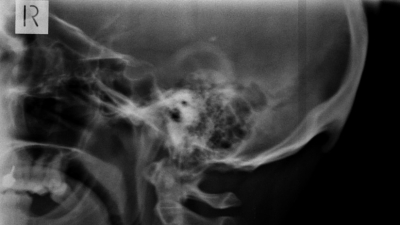

La protuberancia, que puede superar los 20 milímetros, aparece de forma "significativamente más probable" entre las personas jóvenes, según un estudio científico.